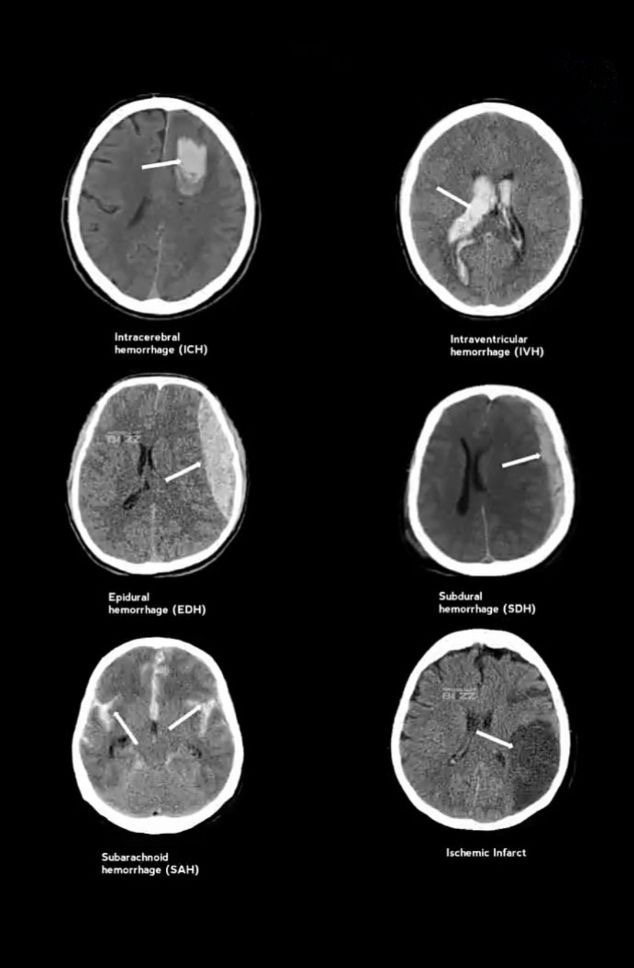

EXTRA-AXIAL HEMORRHAGES

Epidural Hemorrhage (EDH)

Cause: Middle meningeal artery injury (trauma)

CT Findings:

- Biconvex / lentiform shape

- Does not cross suture lines

- Classically associated with lucid interval

Subdural Hemorrhage (SDH)

Cause: Bridging vein tear

- Crescent-shaped collection

- Crosses suture lines (not midline)

Acute → white – hyperdense

Chronic → black – hypodense

Subarachnoid Hemorrhage (SAH)

Cause: Berry aneurysm rupture / trauma

- Hyperdensity in sulci, cisterns, fissures

- “Star-shaped” basal cisterns

- Sudden worst headache of life

INTRA-AXIAL HEMORRHAGES

Intracerebral / Intraparenchymal Hemorrhage (ICH)

Cause: Hypertension, cerebral amyloid angiopathy

- Localized hyperdense bleed within brain parenchyma

- Surrounding hypodense edema

- Common sites: basal ganglia, thalamus, pons, cerebellum

Intraventricular Hemorrhage (IVH)

Cause: Extension of ICH / neonatal germinal matrix bleed

- Hyperdense blood layering in ventricles

- Ventricular dilatation → hydrocephalus

ONE-LINE MEMORY AID

CT Rules to Remember:

Blood = White

Ischemia = Dark (late)

Extra-axial → shape matters

Intra-axial → location matters